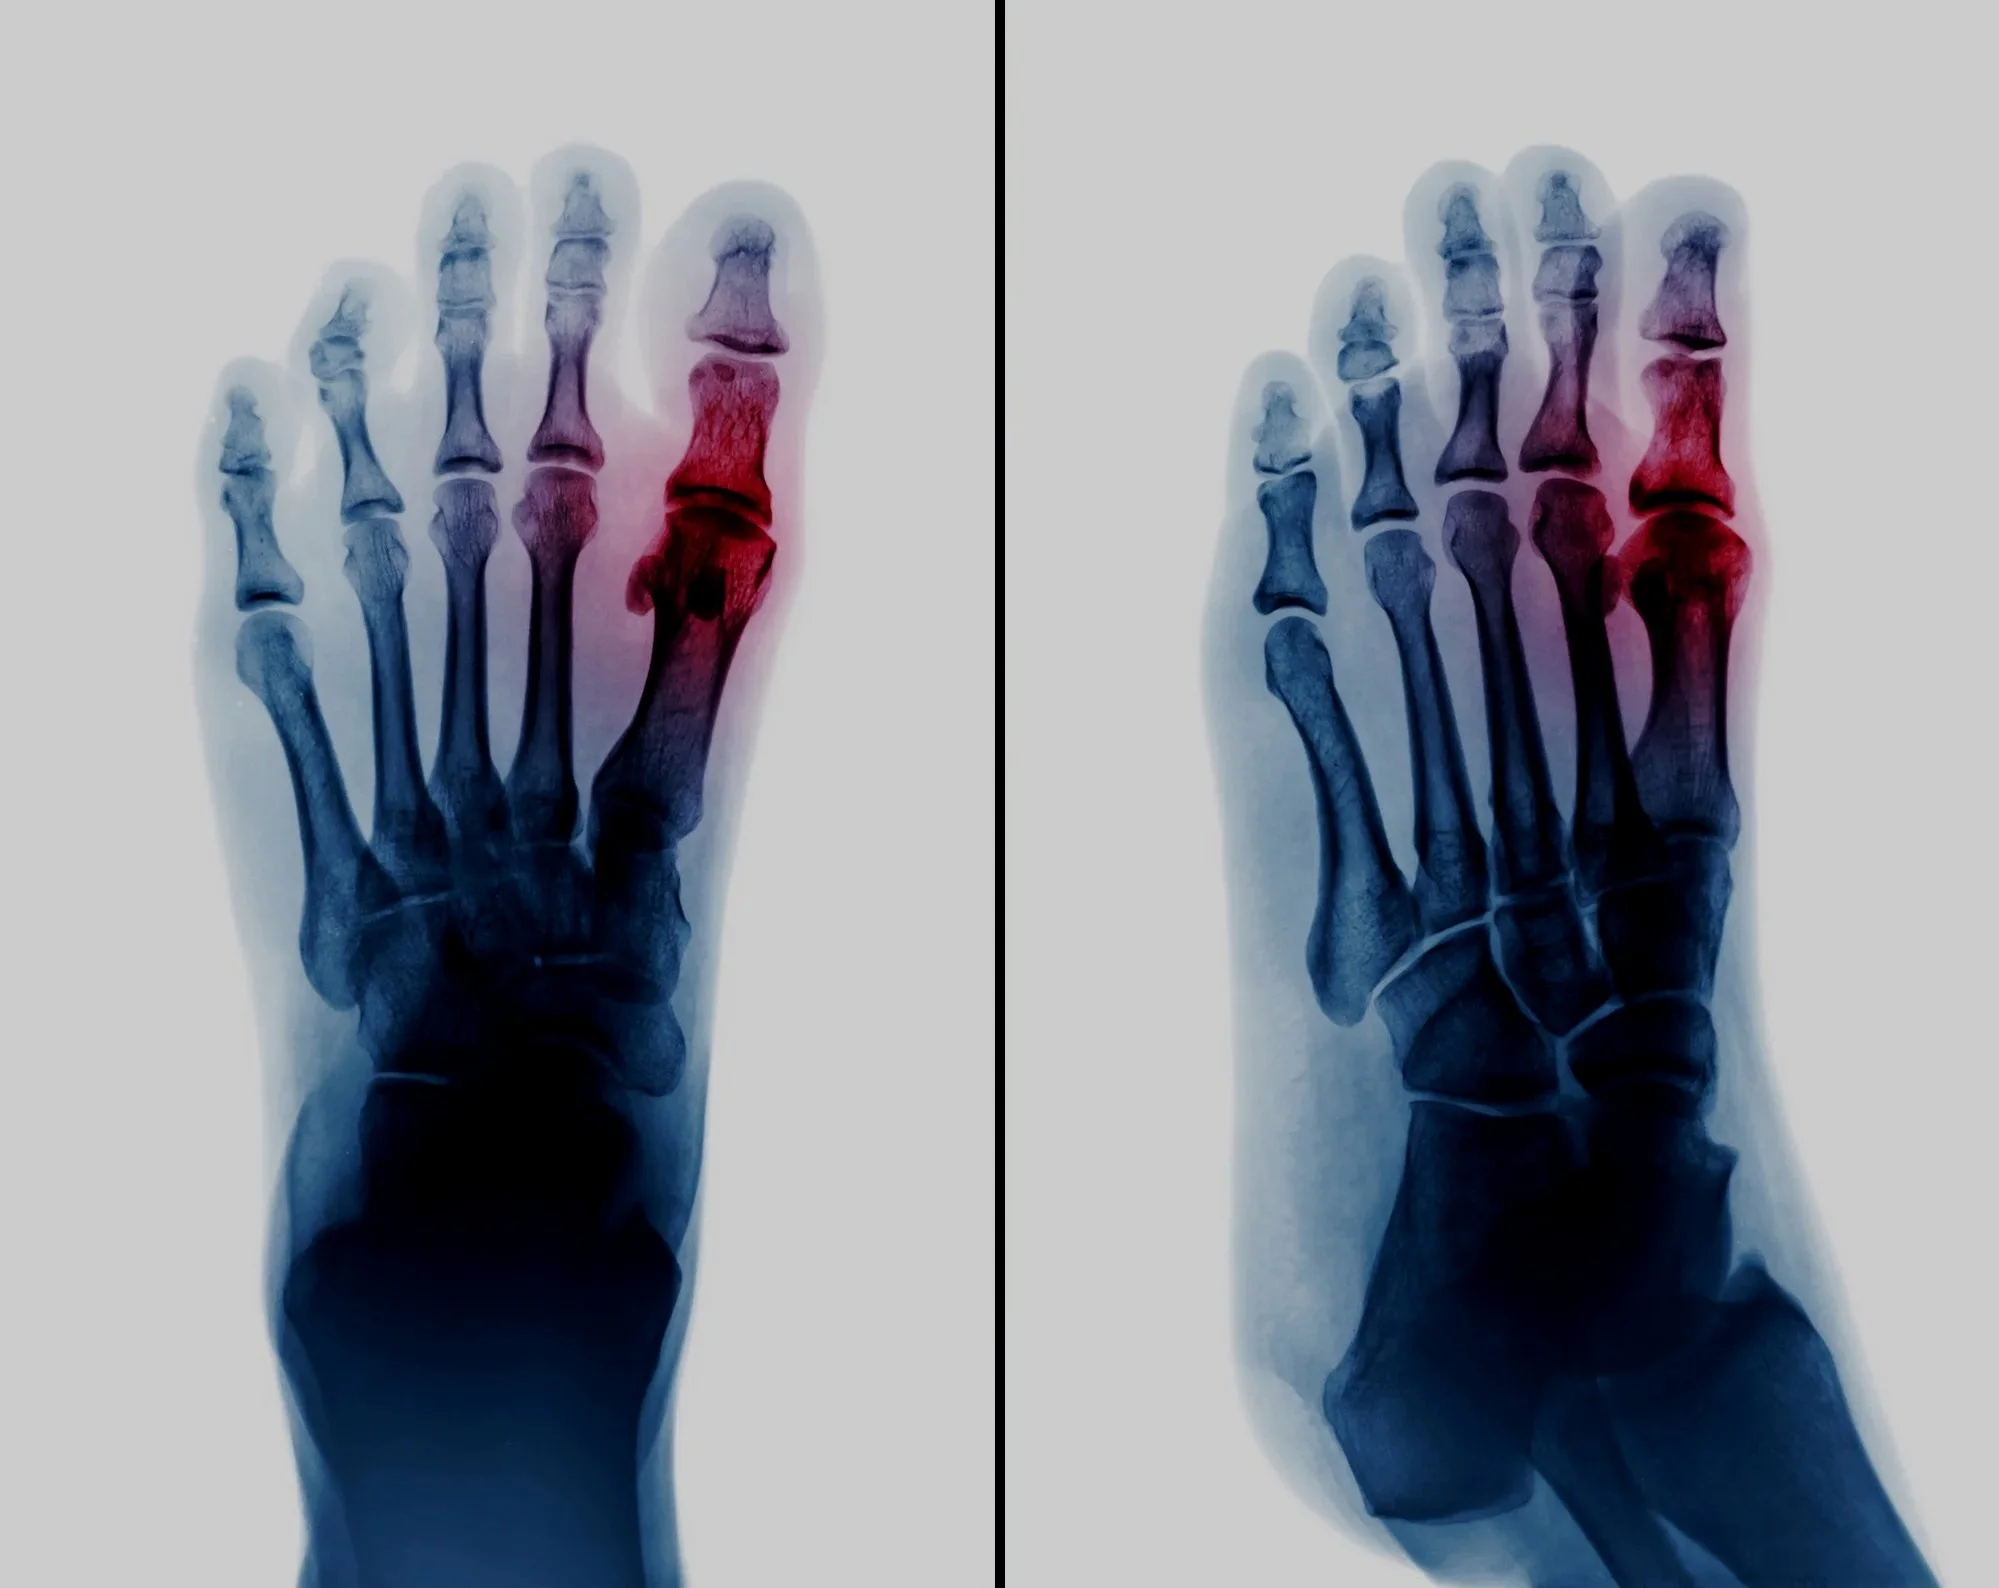

Hallux Limitus/ Rigidus

Cheilectomy Procedure

Arthritic big toe joint arthroplasty surgery. Joint preserving procedure, which may improve the range of movement at the joint. Read more >>